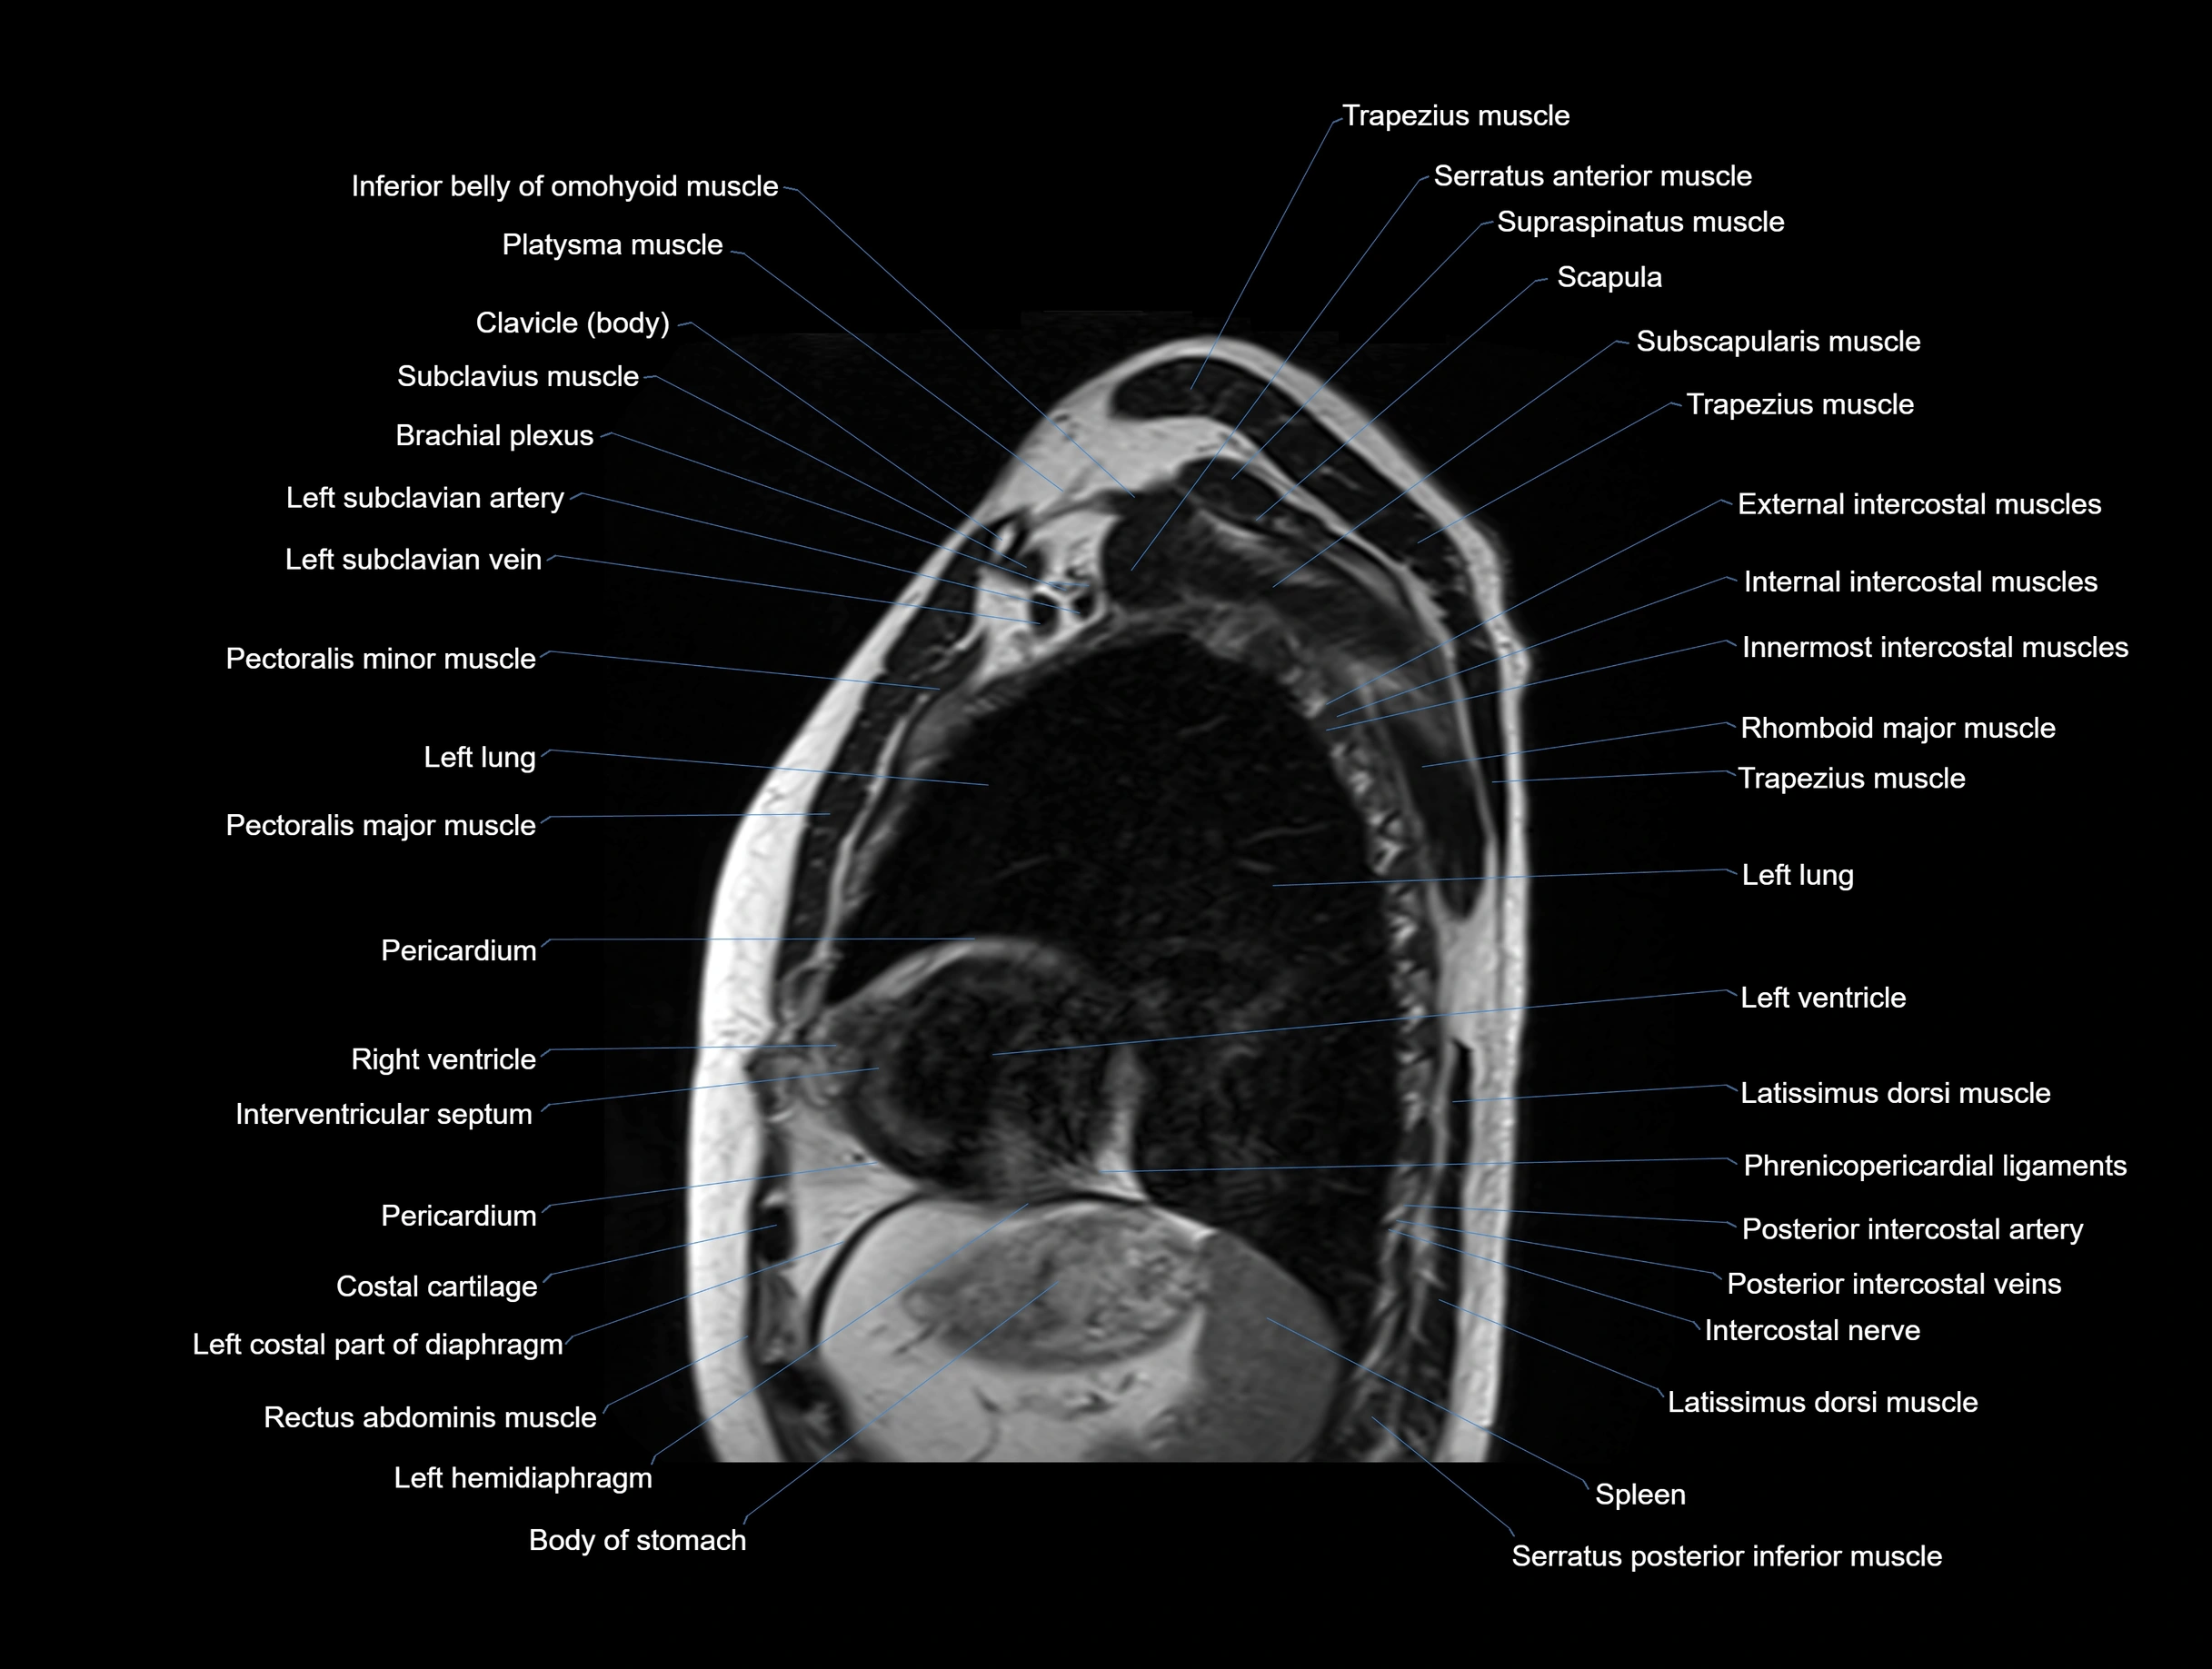

MRI images